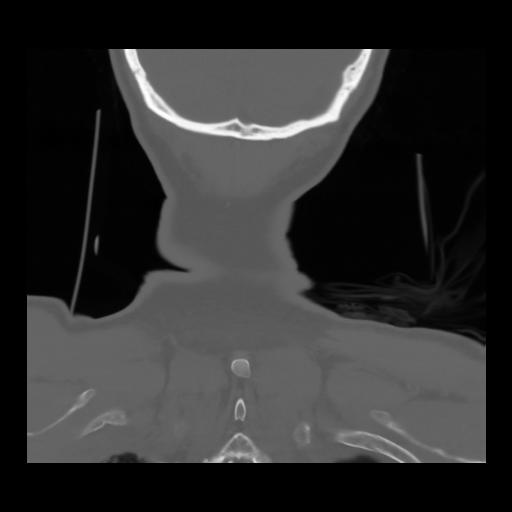

13 P.BLANDAS,,Coronal,2.000,P.BLANDAS,Coronal,